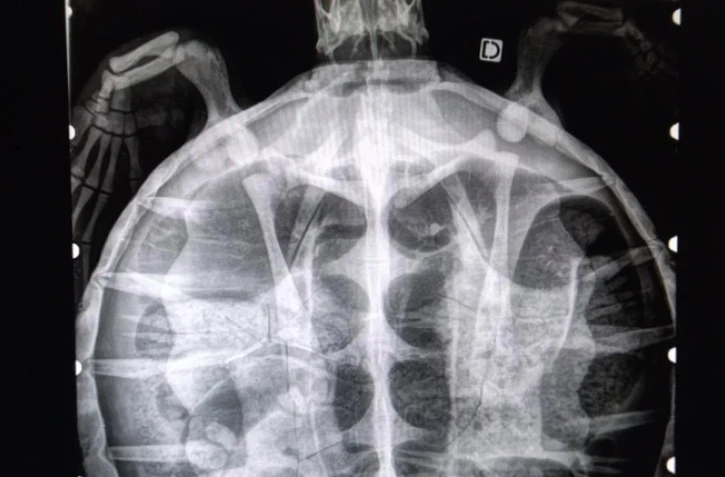

L’autopsie a confirmé de nombreuses fractures des os du plastron et de la dossière, dont une fracture ouverte du plastron.